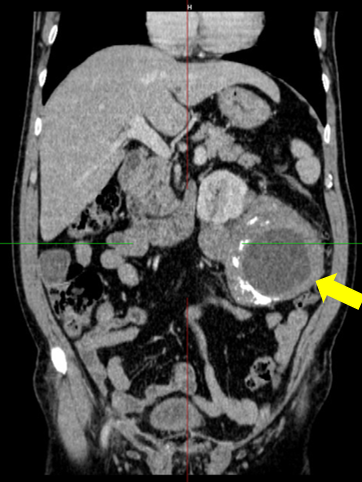

Chụp cắt lớp vi tính ổ bụng:

Hình 4: Hình ảnh chụp cắt lớp vi tính bụng: chưa phát hiện tổn thương bất thường